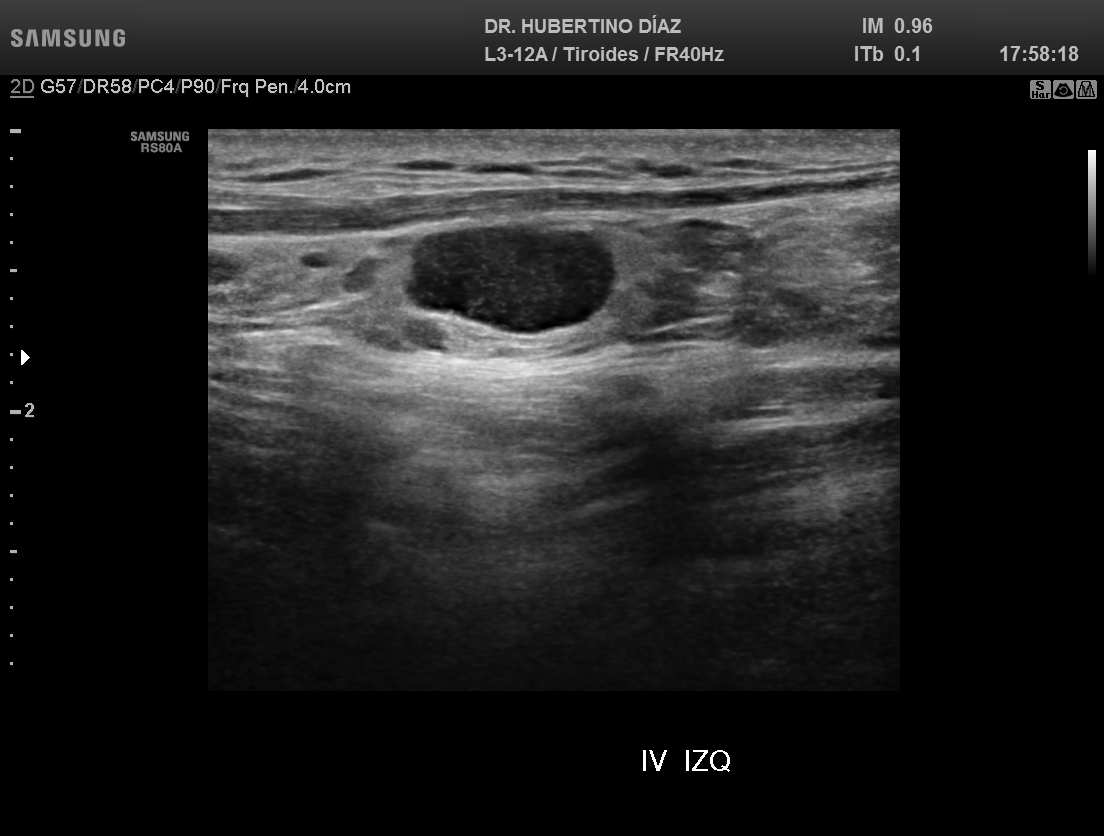

ECOGRAFÍA DE TIROIDES

Ecografía de tiroides en Lima para la evaluación de nódulos...